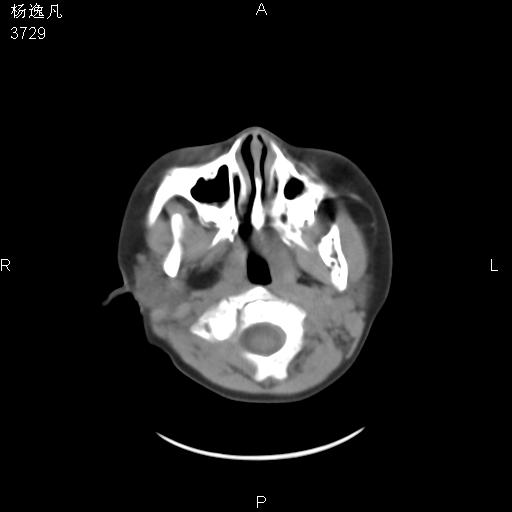

男性,5岁,面部受外伤,余无特殊

软组织窗

1、右面部及颞部软组织肿胀。

2、腺样体肥大。

头颅ct平扫未见明确外伤性征象,右侧面部及颞部软组织肿胀,后鼻腔软组织影增大,增厚,鼻咽顶部变窄,考虑鼻咽腺样体增值肥厚。